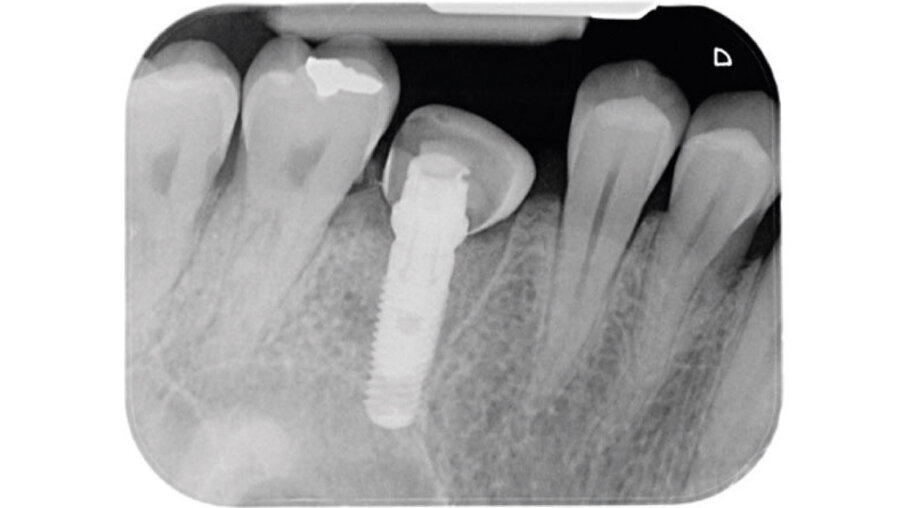

Dopo l’esecuzione dell’anestesia locale, il dente è stato rimosso e l’alveolo pulito dai residui del legamento parodontale. È stato inserito l’impianto (Zimmer TSV, Zimmer, Parsippany) 4.1 x 11,5 TSVM posizionato seguendo il protocollo consigliato dal produttore (Fig. 3). L’impianto è stato inserito a livello della cresta alveolare. È stato avvitato lo scan-abutment (Zfx Intrascan Matchholder, Zfx,). È stata rilevata un’impronta ottica intra-operatoria dell’emiarcata in cui è stato posizionato l’impianto con lo scan abutment (Fig. 3). Il gap tra l’osso vestibolare e l’impianto è stato riempito con Bio-Oss (Geistlich Pharma) (Fig. 4). Al termine della chirurgia è stato progettato e fresato il provvisorio, che è stato applicato appena pronto, dopo aver inserito la matrice in collagene volumetricamente stabile Fibro-Gide (Geistlich Pharma) precedentemente imbibita con il gel a base di polinucleotidi e acido ialuronico Regenfast (Officine Bio-Farmaceutiche Mastelli), al di sotto della vite stessa (Figg. 5, 6). Data l’accuratezza della vite non sono state necessarie suture. Al termine della procedura è stata eseguita una radiografia di controllo (Fig. 7).

Fig. 7_Radiografia di controllo dopo il posizionamento della vite di guarigione customizzata.